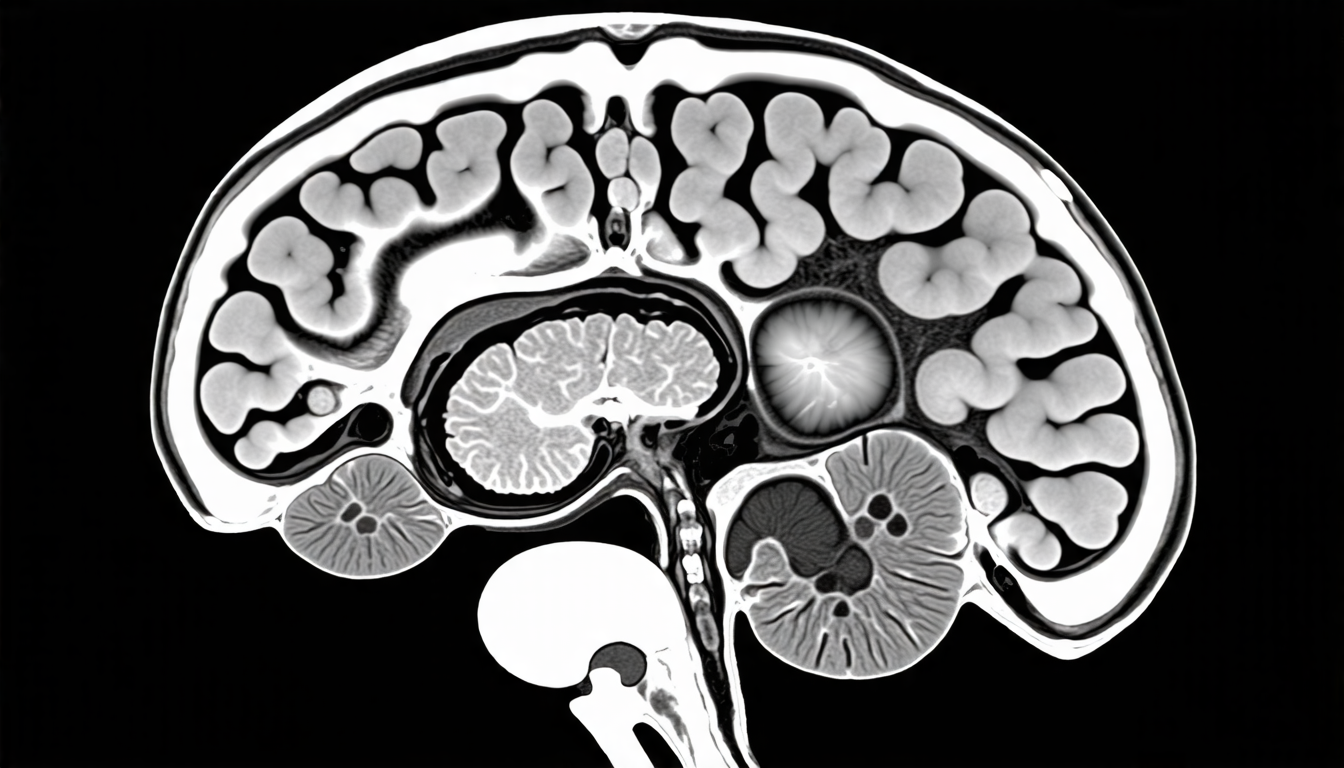

Enter deep learning, which has been hailed as a game-changer in medical imaging analysis. In a recent study published in a leading scientific journal, researchers developed a novel neural network architecture designed specifically for segmenting ischemic stroke lesions from magnetic resonance imaging (MRI) scans.

The new algorithm combines several advanced techniques to achieve high accuracy and robustness. It uses a dense convolutional neural network as its core, which is capable of learning complex patterns in the MRI data. The network also incorporates self-organized operational neurons, channel and space compound attention mechanisms, and double squeeze-and-excitation blocks – all designed to improve performance on challenging segmentation tasks.

But what really sets this study apart is its focus on real-world clinical challenges. The researchers used a multimodal input strategy, combining data from multiple MRI modalities – diffusion-weighted imaging (DWI), apparent diffusion coefficient (ADC), and enhanced DWI – to improve segmentation accuracy.

This approach allowed the algorithm to capture complementary information from each modality, resulting in more accurate lesion boundaries and improved robustness. The researchers also evaluated their algorithm on a dataset of 20 additional MRI scans, with encouraging results that suggest broad applicability to real-world clinical scenarios.